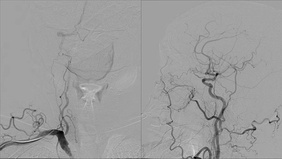

Fusiform Posterior Cerebral Artery Aneurysm Coil Embolization

By Vikalpa DAMMAVALAM

Published on February 24, 2026